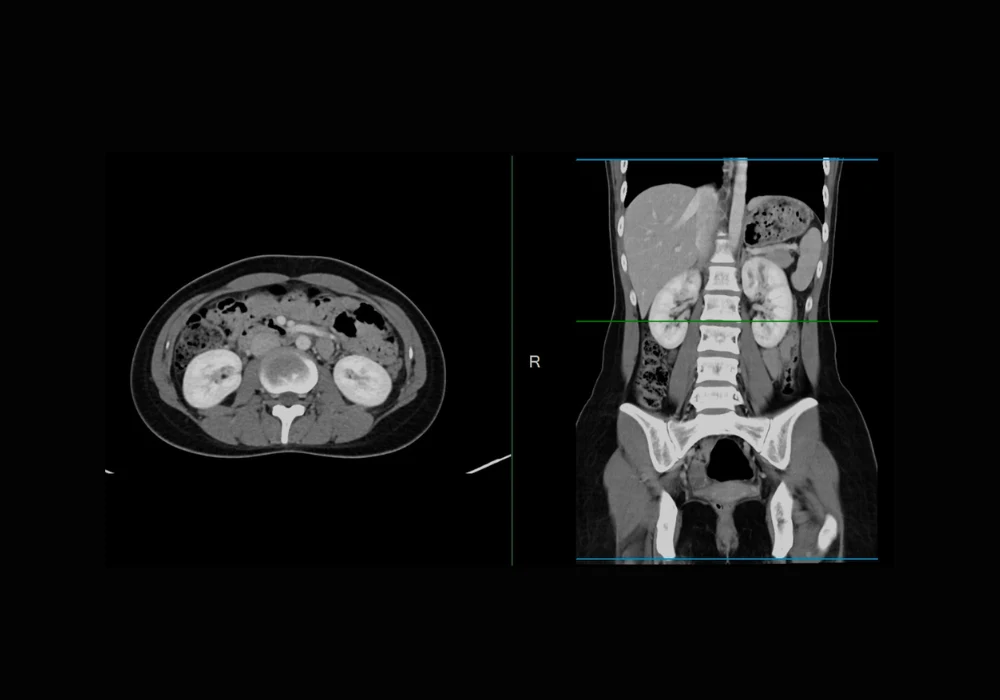

Performance gains were especially apparent for challenging organs such as the pancreas, adrenal glands and duodenum. These structures often pose difficulties due to low contrast or anatomical complexity. The new model delivered better boundary delineation, greater completeness and clearer separation of adjacent structures. Visual comparisons on 2D slices and 3D volumes further supported these quantitative findings. In terms of runtime and resource usage, all methods showed comparable efficiency, underscoring that the performance gains did not come at the cost of higher computational demand.